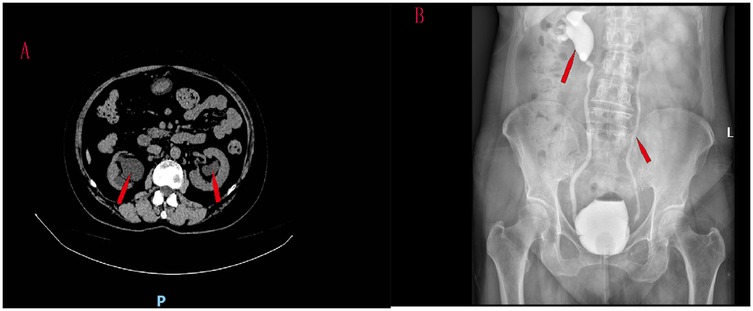

A 61-year-old women was hospitalized with symptoms of recurrent frequent urination, urgent urination and odynuria accompanied by fever and right lumbar pain. The patient had a urine volume of about 50 ml each time, no symptoms of dysuria, and no previous history of tuberculosis, diabetes and lumbar disc herniation. CT scan showed bilateral ureteral hydrodilation (Figure 1A). Preoperative blood creatinine was 167 μmol/L. Tests for tuberculosis were negative. The patient underwent magnetic resonance imaging (MRI) examinations of the brain and spinal cord, and no neurological lesions were found.

Figure 1. CT scan showed bilateral ureteral hydrodilation (A) reflux grade was V in the right ureter and III in the left ureter (B).

Cystography was performed. Vesicoureteral reflux was observed when 80 ml of contrast media was injected into the bladder, and the patient developed a strong urge to urinate. VUR was found in this patient, involving two ureters. Reflux grade was V in the right ureter and III in the left ureter (Figure 1B).